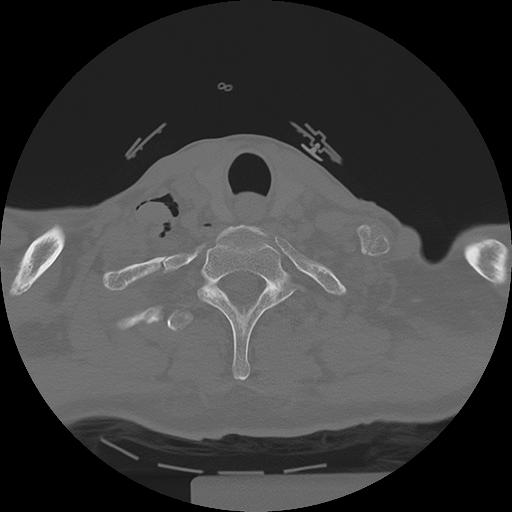

11 HUESO,,Axial,2.0,HUESO,,